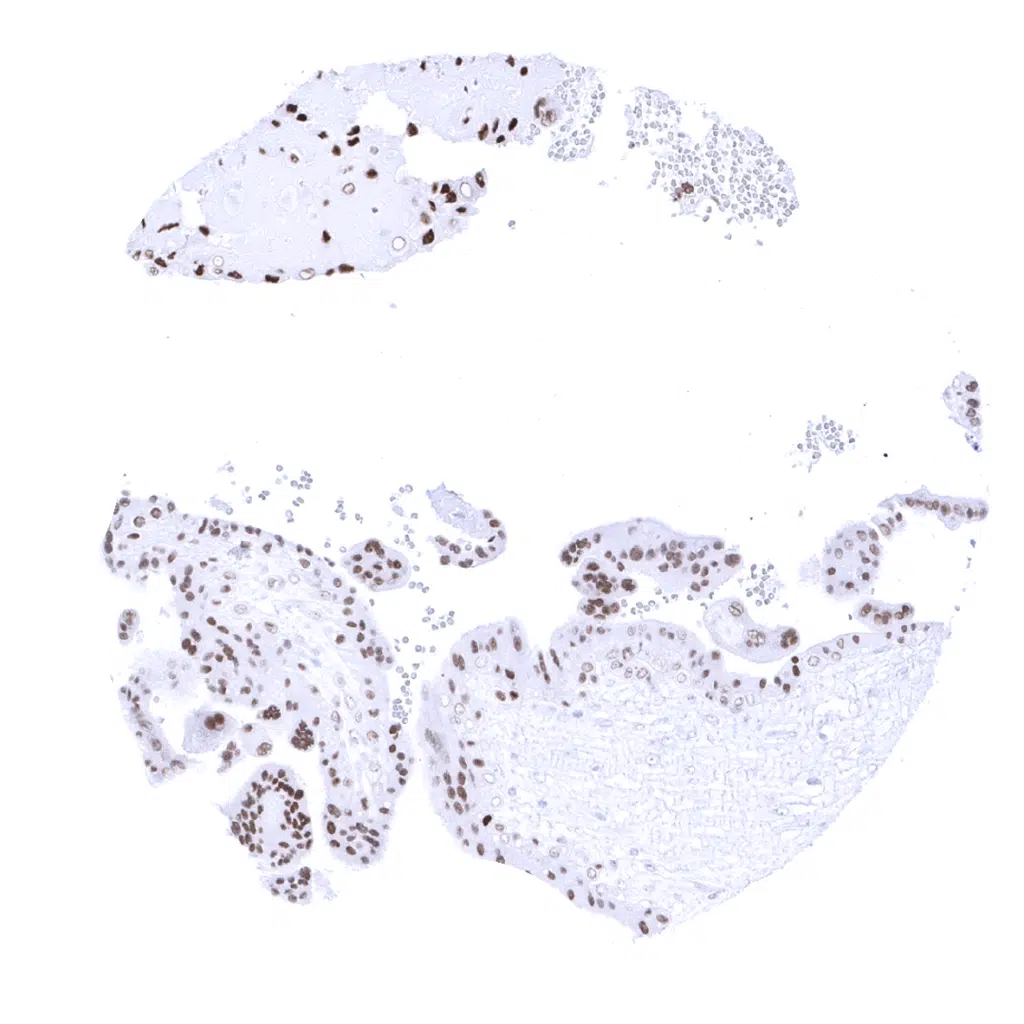

Placenta, mature – GATA3 positivity is seen trophoblast cells. Staining intensity decreases during maturation.